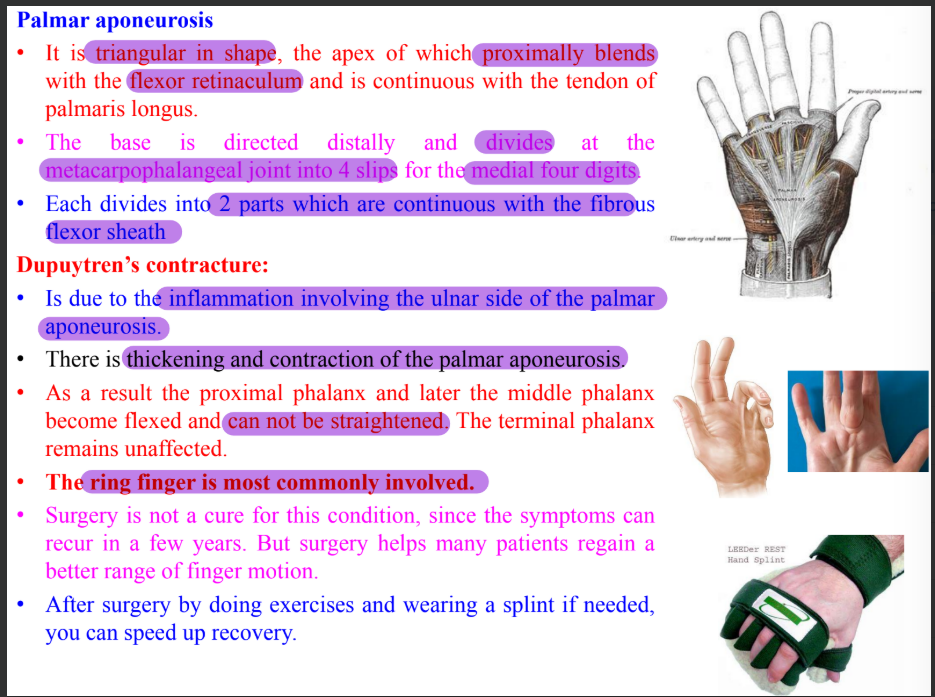

Clinical correlation of hand

Intrinsic muscles of hand

Four thenar muscles

Abductor pollicis brevis

Flexor pollicis brevis

Opponens pollicis brevis

Adductor pollicis brevis

Four hypothenar muscles

Palmaris brevis

Abductor digiti minimi

Flexor digiti minimi

Oppenens digiti minimi

Four lumbricals

Three palmar interossei

Four dorsal interossei